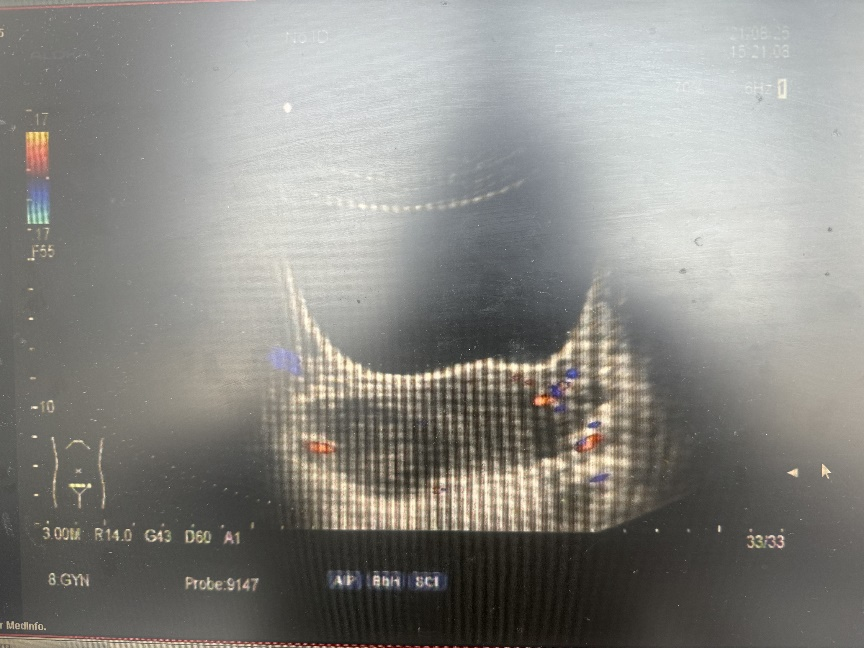

妇科超声(2021-08-25 本院):子宫前位,大小:49mm*49mm*35mm,宫壁回声均匀,形态规则,轮廓清晰。子宫内膜厚度15mm,宫颈长37mm,厚26mm。右附件见45mm*36mm*28mm囊性占位,部分液体内可见细小光点,透声性差。左附件区未见明显异常。子宫声像图提示:右侧卵巢囊性占位,考虑巧克力囊肿(GI RADS3类)。

3、口服地诺孕素,2mg,QD,3月(2021.08-2021.11),复查B超(2021.12.01)子宫前位,大小:40mm*38mm*33mm,宫壁回声均匀,形态规则,轮廓清晰。子宫内膜厚度9mm。右附件见15mm*12mm*13mm囊性占位,部分液体内可见细小光点,透声性差。左附件区未见明显异常。子宫声像图提示:右侧卵巢囊性占位,考虑巧克力囊肿(GI RADS3类)。CA-125:38U/ml。血常规:PLT:33*109/L,患者痛经明显减轻,VAS:3分。继续给予地诺孕素片原方案3个月口服(2021.11-2022.02)。复查B超(2022.02.16)子宫前位,大小:50mm*44mm*31mm,宫壁回声均匀,形态规则,轮廓清晰。子宫内膜厚度8mm。双附件未探及异常。子宫声像图提示:盆腔未见明显异常。CA-125:17.4U/ml。血常规:PLT:23*109/L。患者无痛经症状,VAS:0分。